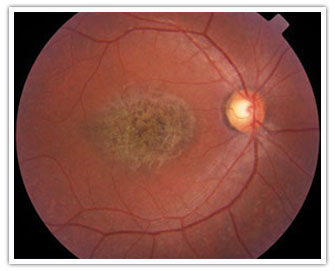

Retinografía, Agujero Macular

¿Qué son los Agujeros Maculares y cuál es su tratamiento?

La Mácula es el tejido retinal responsable de la visión central y firmemente adherido a ésta, está el Vítreo. El Vítreo con la edad se contrae, se separa de la retina y en ocasiones causa levantamientos de la mácula e incluso agujeros. Es menos frecuente que los agujeros se formen de novo.

Los agujeros maculares completos causan distorsión y pérdida de visión central.

Es importante consultar un médico oftalmólogo ante el menor cambio en la visión, puesto que su detección temprana mejora el pronóstico. El tratamiento para los casos avanzados es la cirugía de vitrectomía, retirando el gel vítreo y la membrana que cubre el agujero; es necesario colocar gas intraocular.